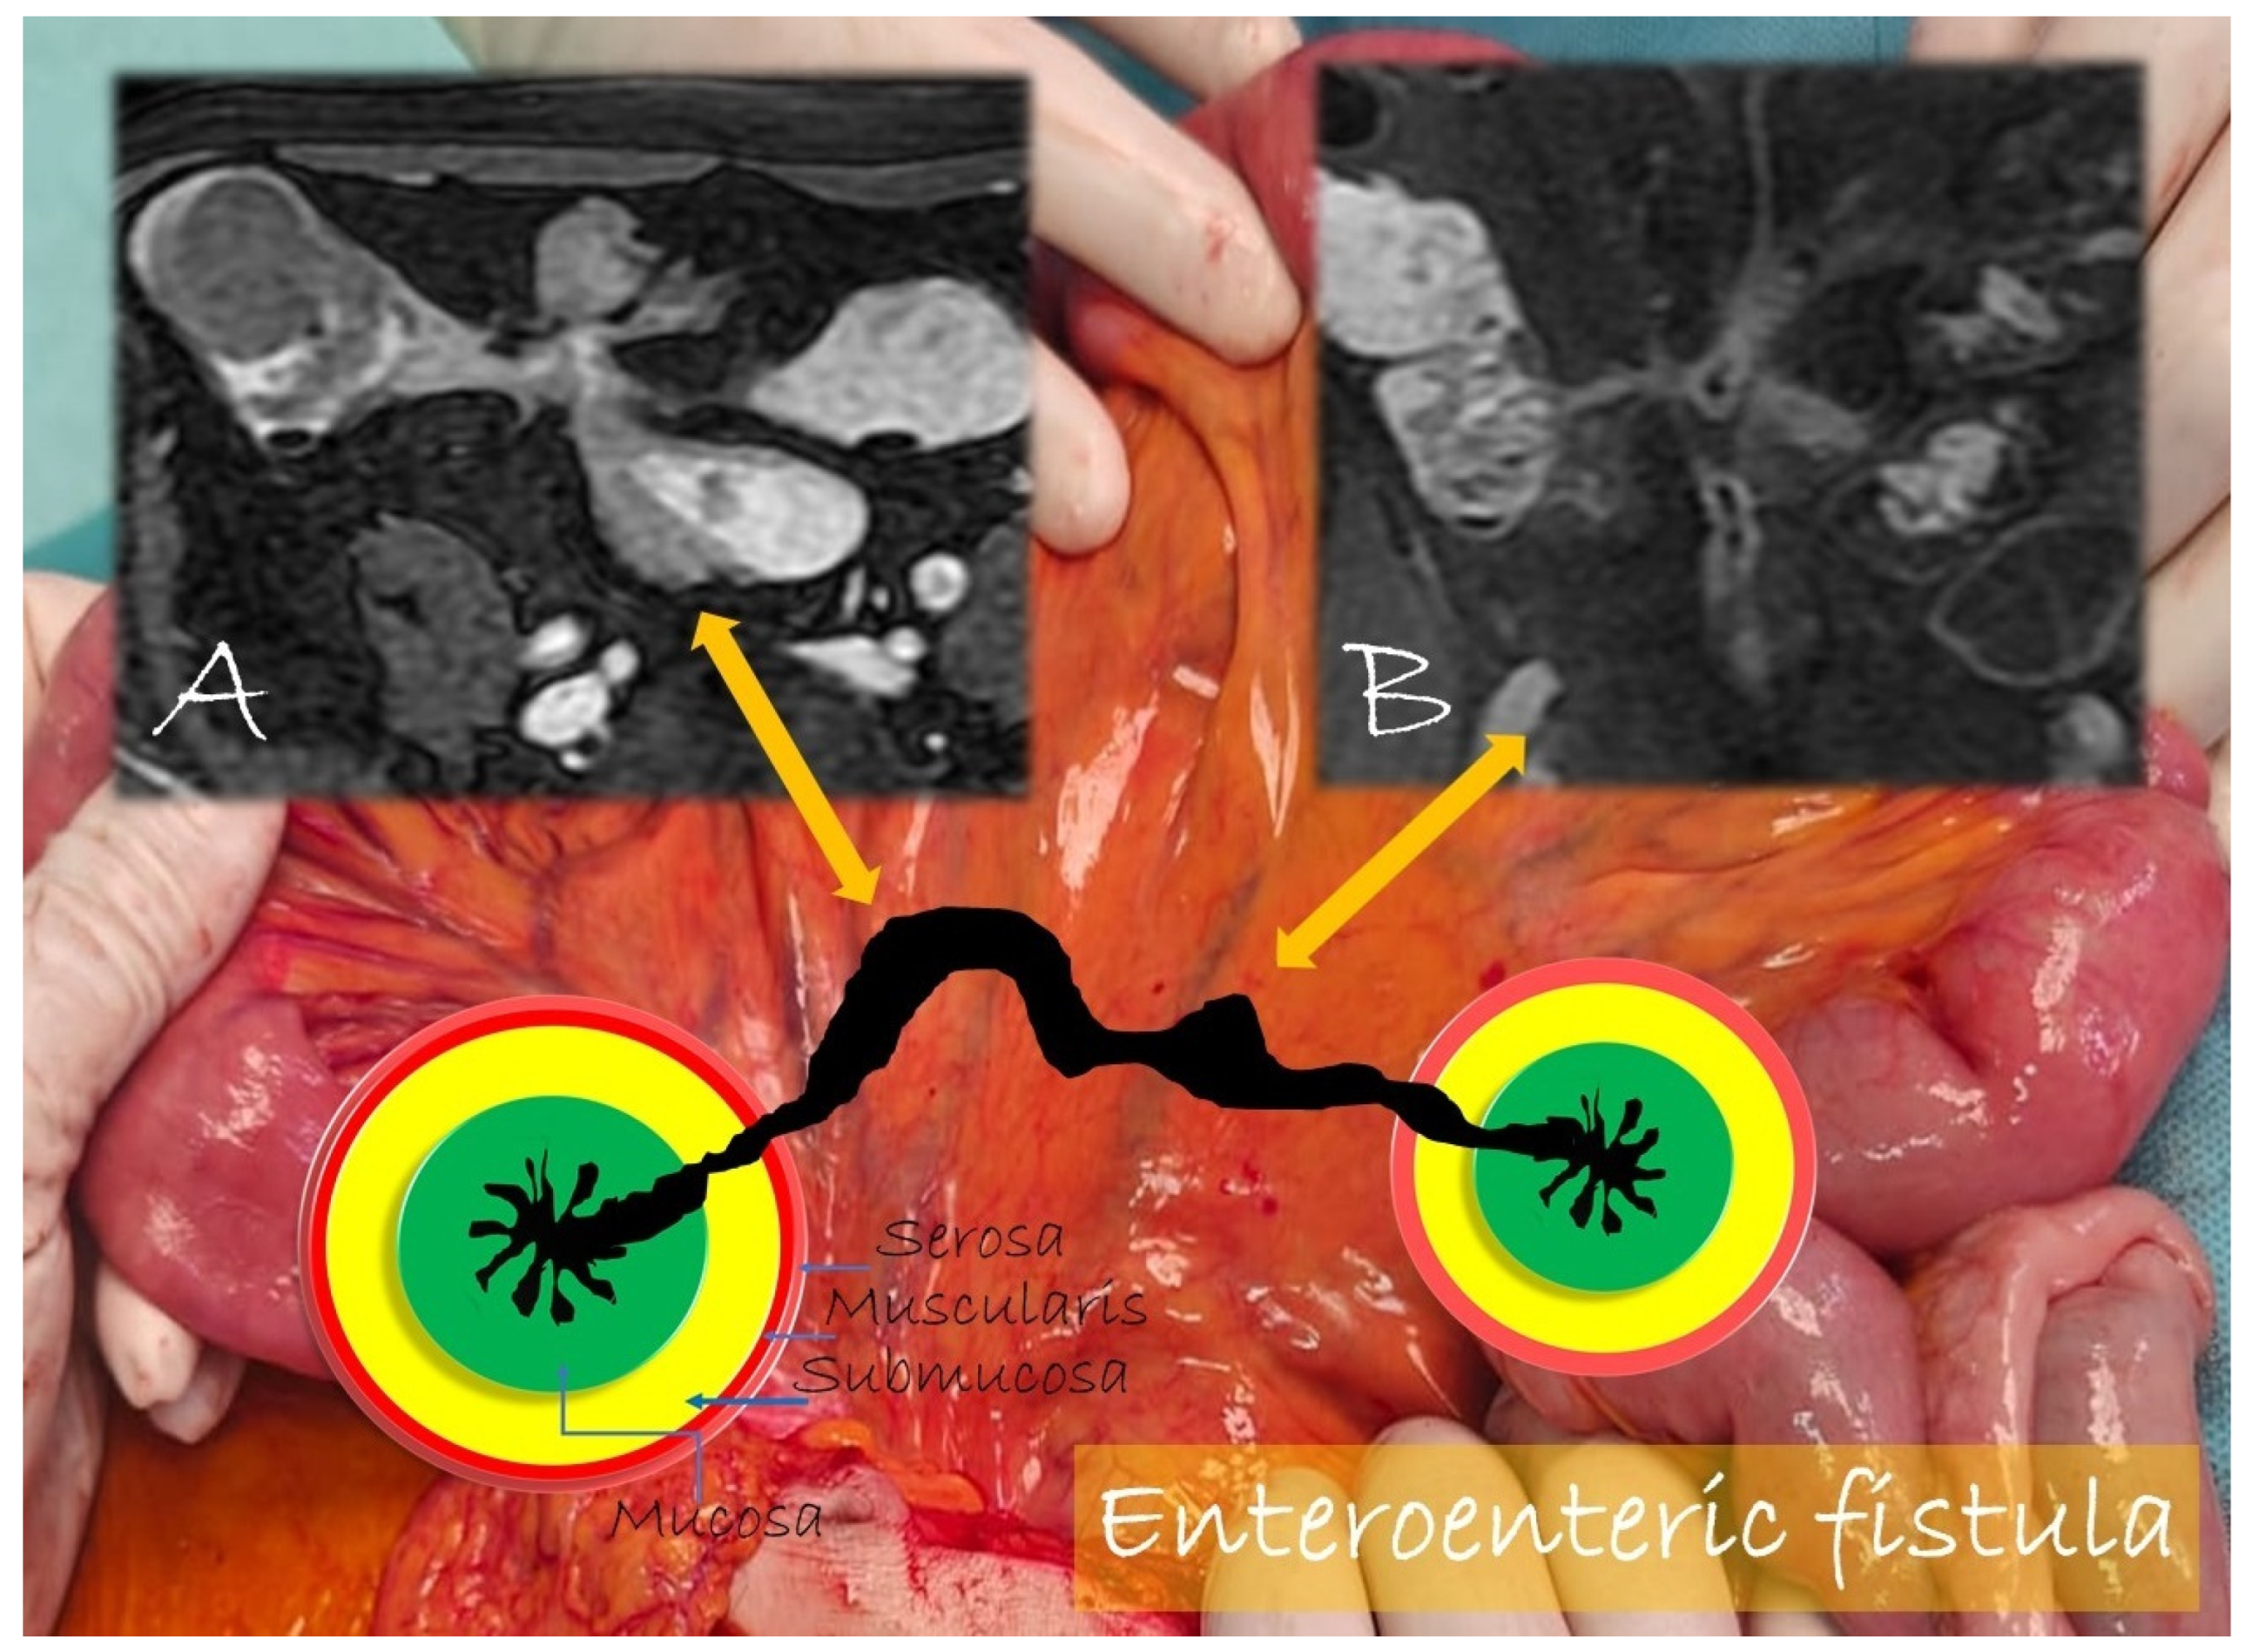

Unlike the sinus tracts, a fistula is defined as a pathologic channel connecting two or more epithelialized surfaces [11]. Fistulae can be simple (single extra enteric tract: enter enteric, enter colic, enter vesical, enterocutaneous, or rectovaginal) or complex (branching and intersecting fistulas, sometimes with a star-like appearance [5]). They represent a complication in approximately 14–50% of the patients with Crohn’s disease (Figure 9, Figure 10 and Figure 11).

Figure 9.

Pathological junctions of intestinal segments through enteroenteric fistulas, which represents internal fistulas that connect intestinal segments such as ileo-sigmoidal (A) and ileo-colic (B).